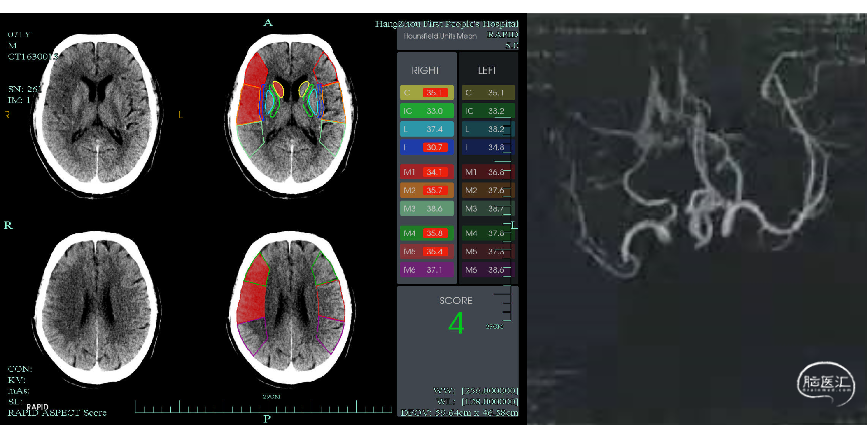

AF,NIHSS 14,ASPECTS 4。

查体:嗜睡,言语不清,双眼右向凝视,左侧鼻唇沟变浅,左侧肌力0级,左侧痛觉减退,左侧病理征(+),NIHSS评分14分。

头颅CTA:右侧大脑中动脉M2段上干闭塞。

CTP:core77ml,mismatch41ml。

DSA:右侧大脑中动脉上干闭塞,右侧大脑前动脉A1段缺如,后交通动脉开放,微导丝微导管导引将Catalyst6头端至于右侧大脑中动脉M1段,保护后交通动脉,微导丝微导管超选M2段。